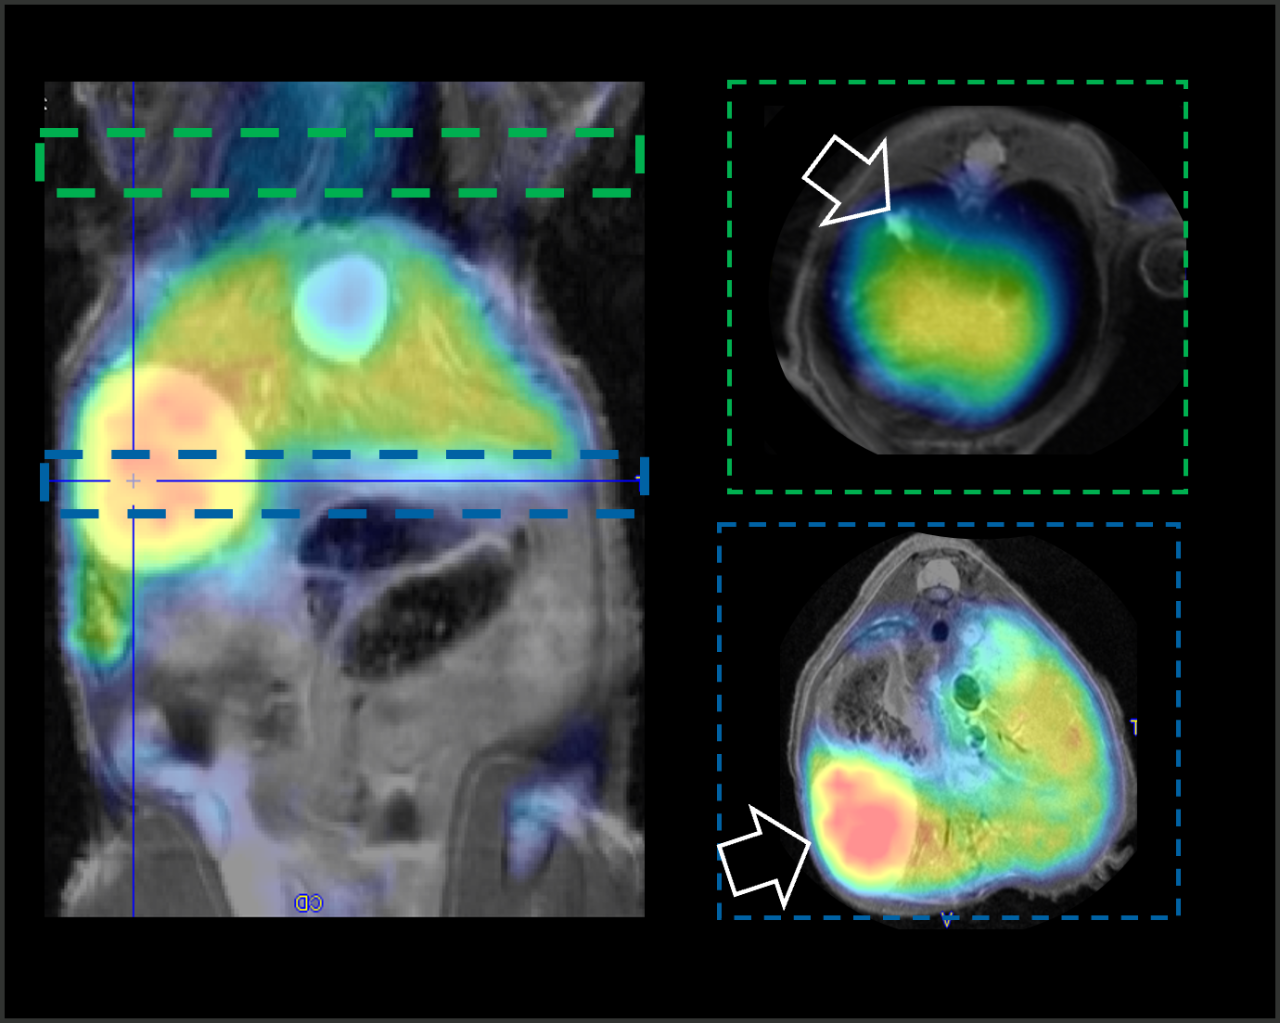

The PET/CT Si78 is a high throughput imaging instrument, dedicated for drug and tracer development for clinical translation . It combines highest PET sensitivity with fast and low dose CT.

The PET/CT Si78 is a molecular imaging system for sequential Positron Emission Tomography (PET) and X-Ray Microtomography (uCT). The fully shielded scanner, the animal welfare solutions and the experimental workflows are designed to support high throughput translational preclinical research in all field s of nuclear molecular imaging research.

ParaVision 360 software offers the complete solutions from subject & study handling, to scan execution, image reconstruction co-registration & image fusion, data analysis and automatic report generation. It easily links imaging data to the most advanced quantitative PET data analysis and kinetic modelling features offered by the PMOD biomedical image quantification software of Bruker.

• PMOD software tools for advanced data analysis and quantification